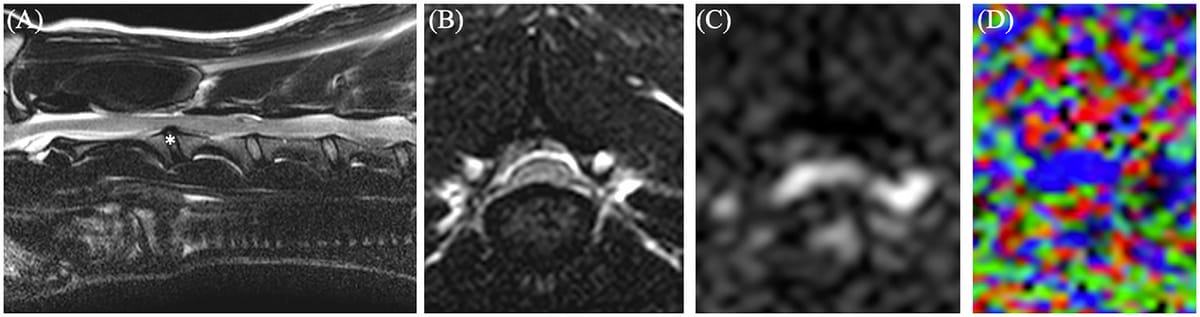

Example of MRI (A, B), diffusion tensor imaging (DTI, C), and fractional anisotropy (D). A, T2-weighted sagittal image of a C2-3 intervertebral disc herniation. The asterisk indicates where transverse images (B–D) were taken. B, T2-weighted transverse at C2-3. C, Registered DTI at the level of C2-3. D, Colored FA map at the level of C2-3 with the spinal cord indicated in blue